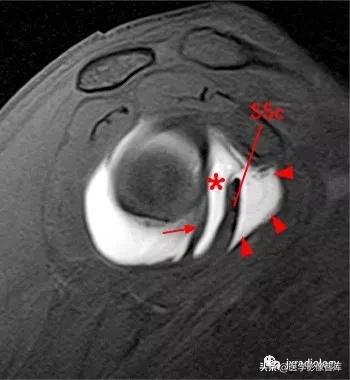

星号:superior subscapularis recess:肩胛下肌上隐窝

箭头:subcoracoid bursa:喙突下滑囊

小箭:middle glenohumeral ligament :盂肱中韧带

SSc:肩胛下肌腱